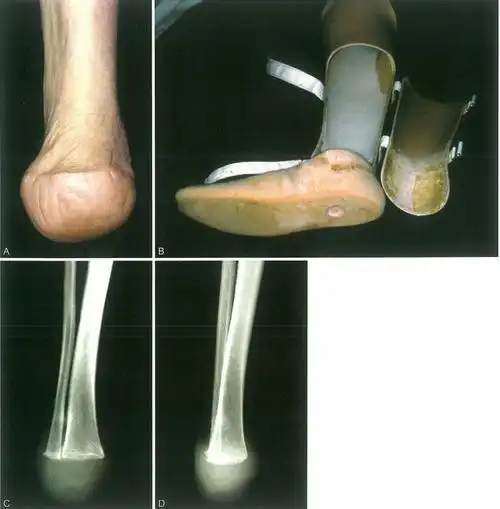

⑵二期手术:syme截肢术⑴一期手术:胫腓骨近端融合术胫腓骨近端融合术